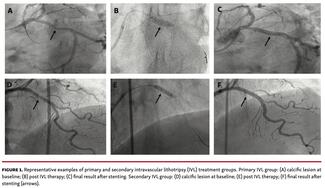

Jack Wei Chieh Tan, MBBS, MRCP; Sridharan Umapathy, MD, DM; Soo Teik Lim, MBBS, MRCP; Yann Shan Keh, MBBS, MRCP; Aaron Sung-Lung Wong, MBBS, MRCP; Ningyan Wong, MBBS, MRCP; Kay-Woon Ho, MBBS, MRCP; Yew Seong Goh, MBBS, MRCP; Khung Keong Yeo, MBBS

The objective of this study was to assess the clinical and angiographic outcomes of coronary intravascular lithotripsy use in an all-comers population with moderate-to-severely calcified coronary lesions